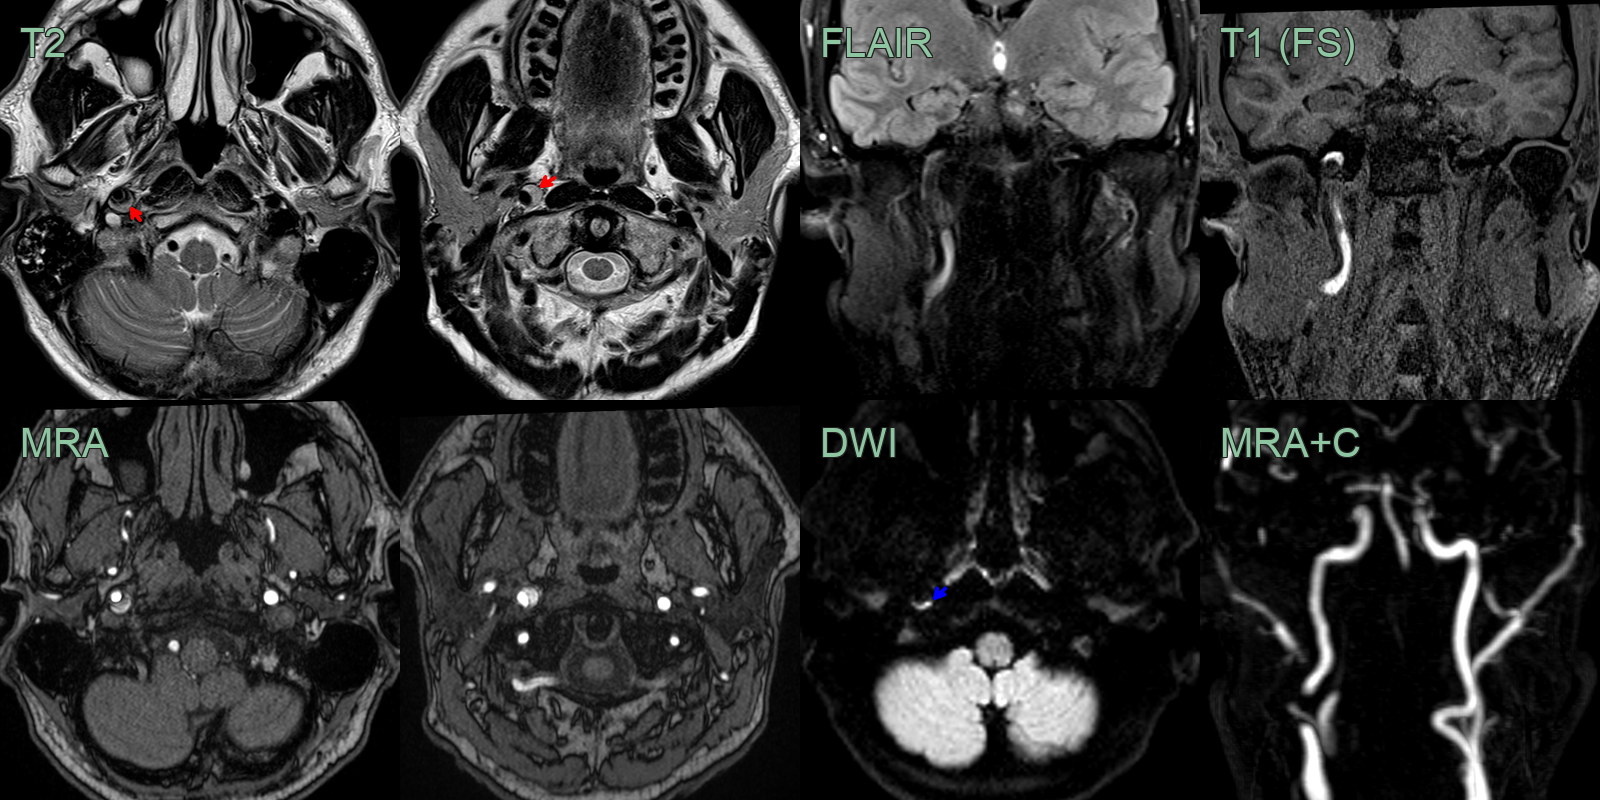

- 50-year-old patient presented with sudden onset right sided neck pain and a Horner's syndrome (blurred vision, right sided miosis and ptosis).

- The initial CT and CTA showed a hyperdense rim around an expanded right ICA below the skull base without a significant stenosis (yellow arrow).

- The T1-weighted imaging showed a T1-hyperintense rim around the ICA (red arrow).

- The mural thrombus also showed diffusion restriction (blue arrow) and blooming on SWI (not shown).